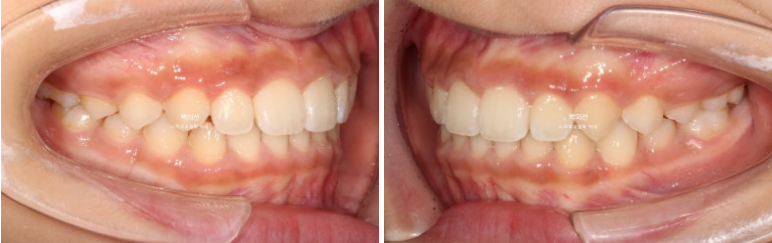

이제 전후 비교 보겠습니다.

23.07~25.07

덧니와 과개교합의 개선입니다.

앞니 돌출의 개선

교합의 개선